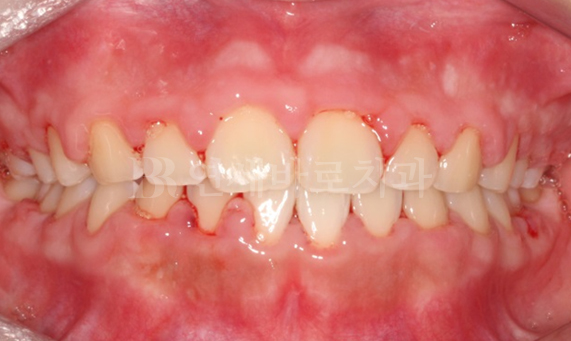

덧니 교정 CASE

-

연세바로치과는 치료법을 준수합니다. 로그인 하시면 Before를 보실 수 있습니다. LOGIN